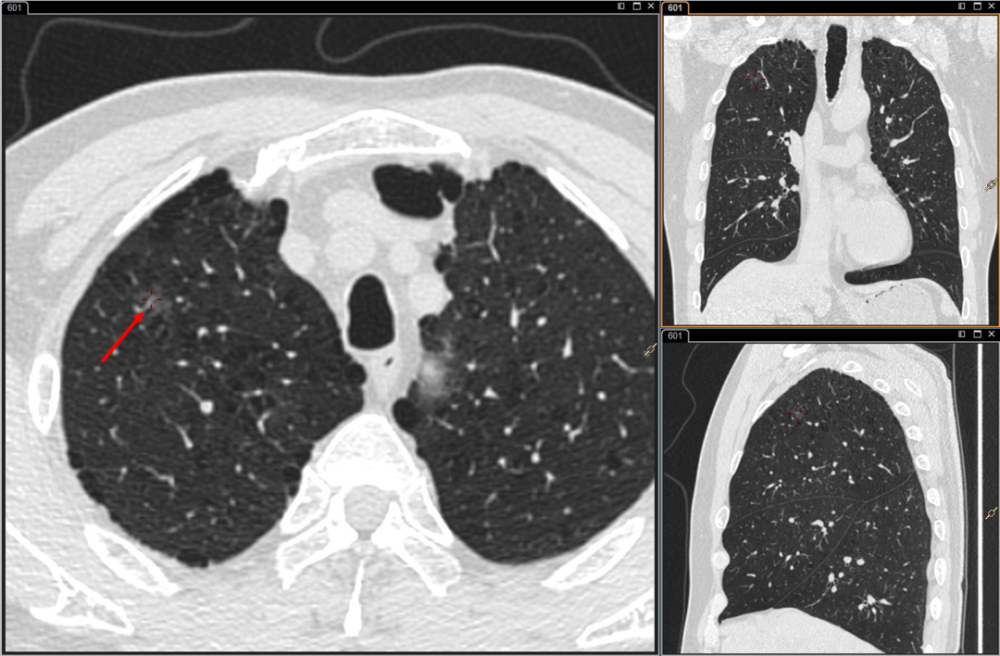

肺磨玻璃結節(GGN)其實是一類特定病症,在CT上面(miàn)顯示肺組織内局部密度增高區域,就(jiù)像磨砂玻璃質一樣(yàng)的淡影,而這(zhè)個區域很有特征性:增生的細胞沿現有的結構和肺泡壁生長(cháng)而不侵犯基質、胸膜或血管,但正常的支氣管和血管都(dōu)還(hái)存在,且不像腫瘤一樣(yàng)的實體病竈。磨玻璃結節與惡性腫瘤還(hái)是有很大區别的,且沒(méi)有傳染性,不會(huì)通過(guò)空氣、氣道(dào)或者氣道(dào)的分泌進(jìn)行傳播。

(圖片來源于百度健康醫典)